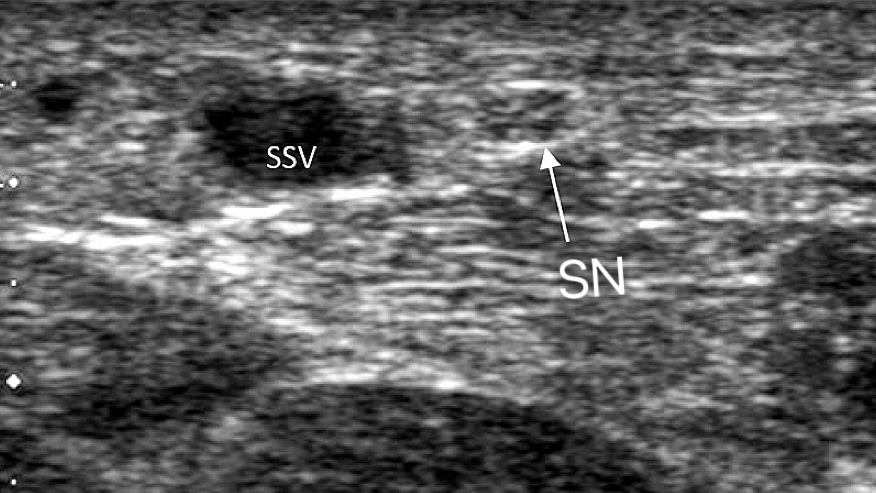

The primary concern during any intervention on the SSV is its intimate relationship with the Sural Nerve (SN) and the Tibial Nerve (TN).

In the distal two-thirds of the lower leg, the Sural Nerve and the SSV are nearly inseparable, often traveling within millimeters of each other. Unlike other regions where the deep fascia acts as a protective barrier, the distal SSV and Sural Nerve often share the same anatomical compartment without a fascial shield.

While ablation uses ultrasound for catheter placement, CHIVA uses it for hemodynamic architecture. We map the exact relationship between the Sural Nerve and the SSV before the first incision is made. This synergy between high-resolution imaging and surgical experience ensures that every ligation is strategic, purposeful, and—most importantly—safe.